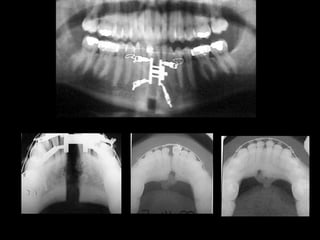

Se observa el número total de órganos dentarios incluyendo

terceros molares.

No hay tratamiento de conductos radiculares

Buen trabeculado óseo de tipo I

Se observa elnúmero total de órganos dentarios incluyendo terceros molares. No hay tratamiento de conductos radiculares Buen trabeculado óseo de tipo I Se observa el número total de órganos dentarios incluyendo terceros molares. No hay tratamiento de conductos radiculares Buen trabeculado óseo de tipo I